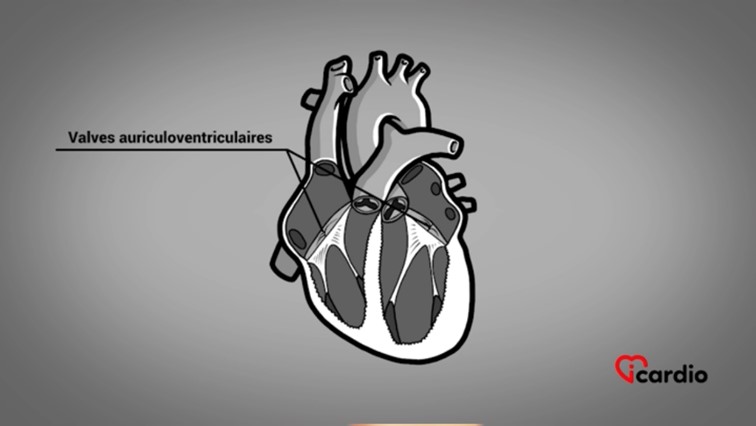

Les 2 autres valves cardiaques sont les valves auriculo-ventriculaires qui séparent les ventriculesLes ventricules sont les 2 cavités inférieures du cœur. Ils sont plus musclés que les oreillettes; ils servent à propulser le sang pour assurer la circulation dans tout le corps. >> des oreillettesLes oreillettes sont les deux cavités supérieures du cœur. Elles agissent comme des réservoirs du sang qui ira remplir les ventricules. >>.

Ces valves sont montées sur les anneaux auriculo-ventriculaires et sont composées de feuillets, de cordages et de piliers musculaires situés à la hauteur des ventriculesLes ventricules sont les 2 cavités inférieures du cœur. Ils sont plus musclés que les oreillettes; ils servent à propulser le sang pour assurer la circulation dans tout le corps. >>.